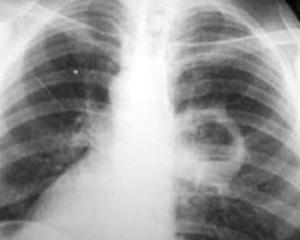

При постукивании над областью абсцесса звук будет приглушенным, а дыхание в этом участке ослаблено. Пораженная сторона вызывает болевые ощущения при дыхании, а рентгенологическое исследование покажет ограниченную тень с различной интенсивностью и размерами.

Острый абсцесс может протекать в легкой, средней или тяжелой форме. Легкая форма характеризуется наличием одиночной полости и незначительной реакцией по периферии на рентгеновском снимке, где четко виден уровень жидкости. Такой абсцесс формируется в течение 8-10 дней, и после его опорожнения наступает полное выздоровление.

Средняя степень тяжести проявляется наличием одиночной полости абсцесса, окруженной значительной зоной пристеночной реакции. Формирование абсцесса происходит медленно на фоне длительной пневмонии. После прорыва полость плохо дренируется, температура снижается нестабильно, часто происходят обострения. Рентгенологическая динамика наблюдается медленно, выздоровление наступает редко, чаще абсцесс переходит в хроническую форму.

Когда произошел прорыв, задача облегчается, ведь человек может выделять мокроту «полным ртом», особенно при перемене положения тела (например если лечь на бок). На рентгеновском снимке все выглядит как полость с уровнем жидкости и слоем газа над ней.